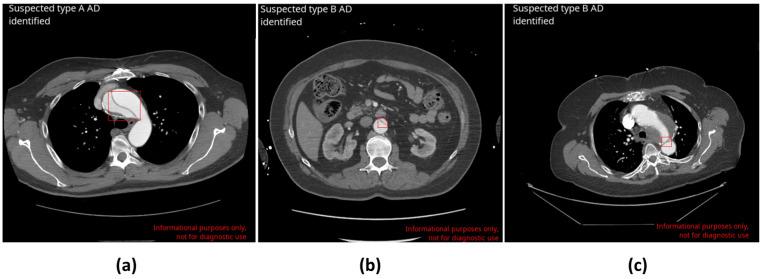

This multicenter retrospective study evaluated the diagnostic performance of a deep learning (DL)-based application for detecting, classifying, and highlighting suspected aortic dissections (ADs) on chest and thoraco-abdominal CT angiography (CTA) scans. CTA scans from over 200 U.S. and European cities acquired on 52 scanner models from six manufacturers were retrospectively collected and processed by CINA-CHEST (AD) (Avicenna.AI, La Ciotat, France) device. The diagnostic performance of the device was compared with the ground truth established by the majority agreement of three U.S. board-certified radiologists. Furthermore, the DL algorithm's time to notification was evaluated to demonstrate clinical effectiveness. The study included 1303 CTAs (mean age 58.8 ± 16.4 years old, 46.7% male, 10.5% positive). The device demonstrated a sensitivity of 94.2% [95% CI: 88.8-97.5%] and a specificity of 97.3% [95% CI: 96.2-98.1%]. The application classified positive cases by the AD type with an accuracy of 99.5% [95% CI: 98.9-99.8%] for type A and 97.5 [95% CI: 96.4-98.3%] for type B. The application did not miss any type A cases. The device flagged 32 cases incorrectly, primarily due to acquisition artefacts and aortic pathologies mimicking AD. The mean time to process and notify of potential AD cases was 27.9 ± 8.7 s. This deep learning-based application demonstrated a strong performance in detecting and classifying aortic dissection cases, potentially enabling faster triage of these urgent cases in clinical settings.

这项多中心回顾性研究评估了一种基于深度学习(DL)的应用程序在胸部和胸腹CT血管造影(CTA)扫描中检测、分类和突出显示疑似主动脉夹层(AD)的诊断性能。回顾性收集了来自美国和欧洲200多个城市、由六个制造商的52种扫描仪型号采集的CTA扫描数据,并通过CINA-CHEST(AD)(Avicenna.AI,法国拉西奥塔)设备进行处理。将该设备的诊断性能与三位美国董事会认证放射科医生的多数意见确定的地面真相进行比较。此外,评估了DL算法的通知时间以证明其临床有效性。该研究包括1303例CTA(平均年龄58.8±16.4岁,男性46.7%,阳性10.5%)。该设备的敏感性为94.2%[95%CI:88.8-97.5%],特异性为97.3%[95%CI:96.2-98.1%]。该应用程序按AD类型对阳性病例进行分类,A型的准确率为99.5%[95%CI:98.9-99.8%],B型的准确率为97.5[95%CI:96.4-98.3]%。该应用程序没有遗漏任何A型病例。该设备错误标记了32例病例,主要是由于采集伪影和模仿AD的主动脉病变。处理并通知潜在AD病例的平均时间为27.9±8.7秒。这种基于深度学习的应用程序在检测和分类主动脉夹层病例方面表现出强大的性能,有可能在临床环境中更快地对这些紧急病例进行分诊。